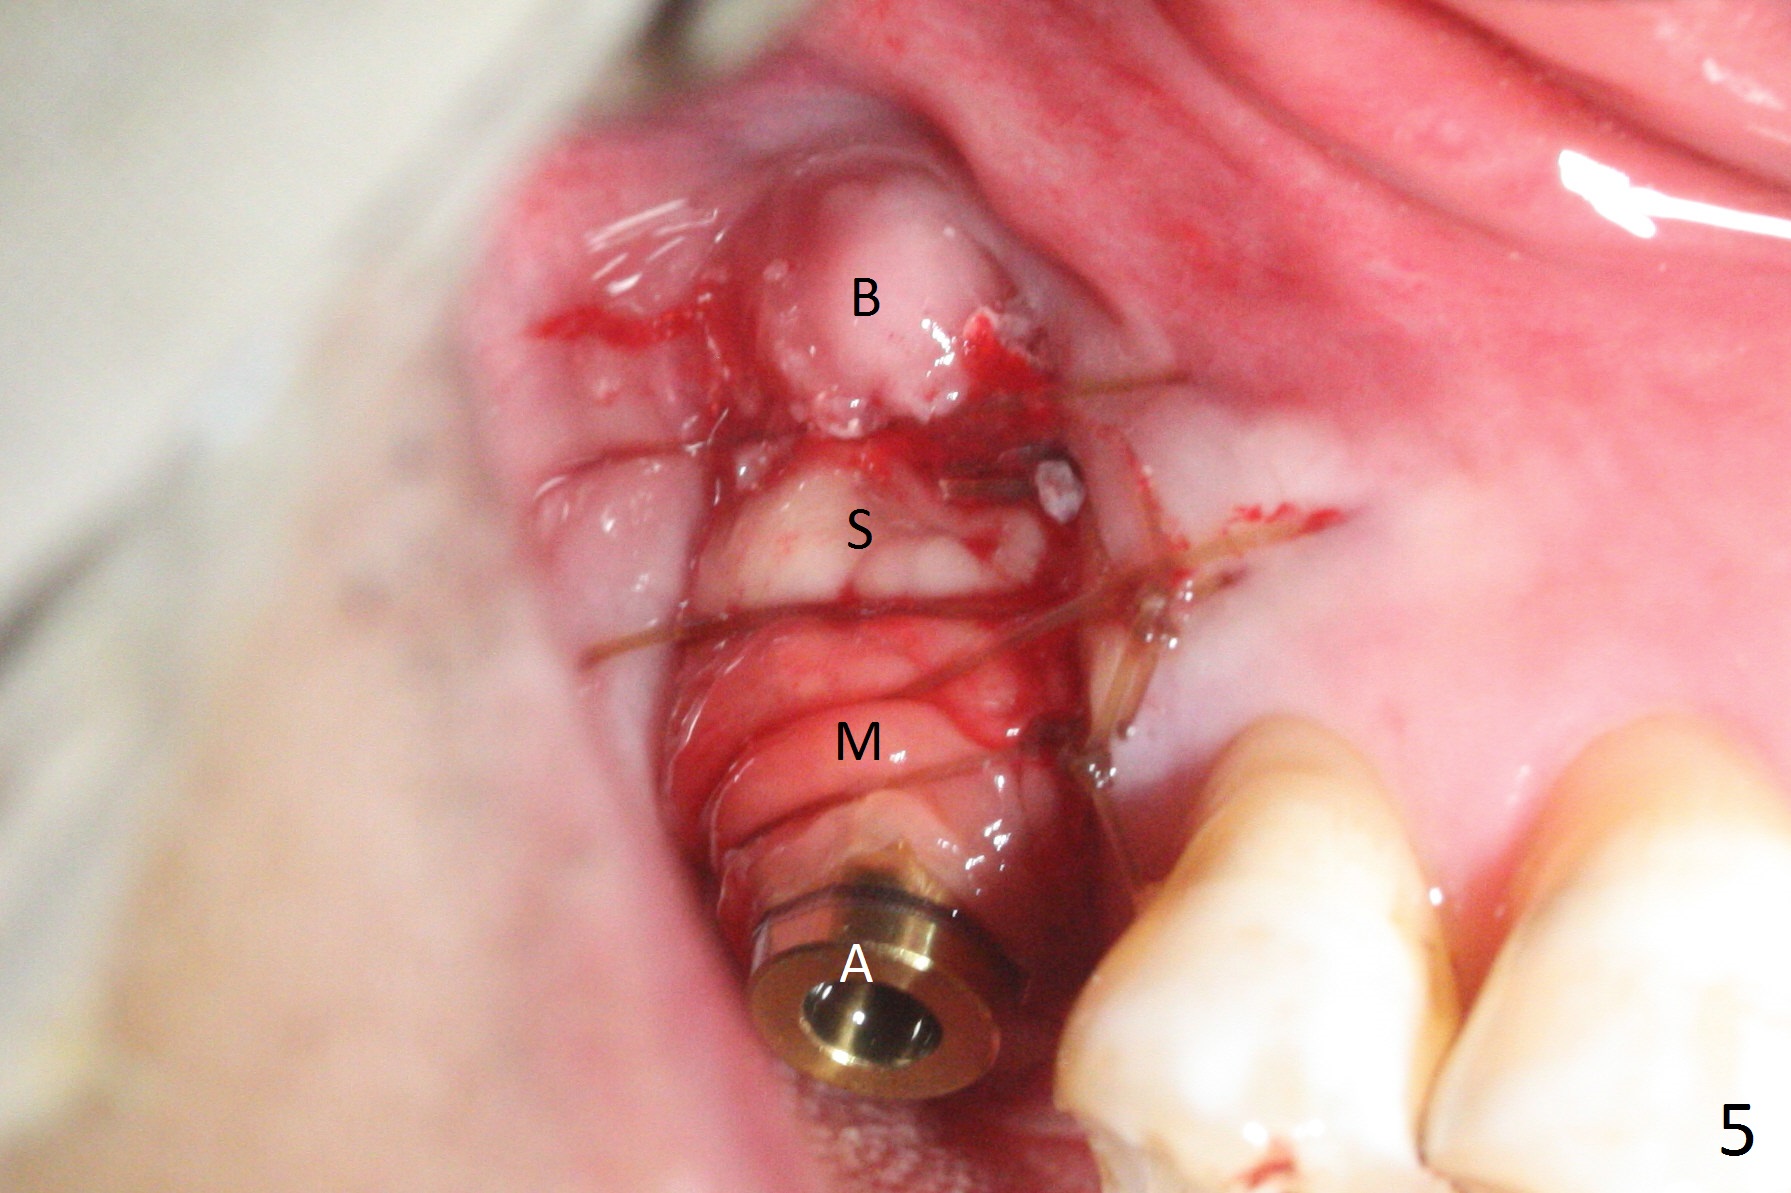

The palatal socket (Fig.1 P, packed with gauze) is intact, but implant trajectory may not be ideal. Buccal to the palatal socket are 2 pieces of the gingiva, buccal (B) and Septal (S). After the septal gingiva is pushed buccally (Fig.2 arrow), the underlying sloped septal bone is exposed (Fig.3 white area). Osteotomy is established as palatal as possible (Fig3 black circle) using DIO Sinus Master Kit, supplemented by Tatum osteotomes and DIO SM 3.8 mm tap drill for final sinus lift (Fig.4). Following further osteotomy using 4.1 and 4.5 mm taps, a 4.5x10 mm implant (Fig.6,7) with insertion torque >65 Ncm. Due to buccal bone loss, the coronal buccal threads are exposed 1-2 mm, which is covered by combination of allograft, autogenous bone and Osteogen. Prior to implantation, PRF plug and bone graft are used for sinus lift. The septal gingiva now is approximately 1-2 mm coronal to the implant plateau (Fig.5 S). The most coronal buccal gingival defect is covered by 3 pieces of PRF membrane (Fig.5 M) against a 6.8x5.5(6) mm abutment (A). Finally the socket is protected by periodontal dressing (Fig.8).